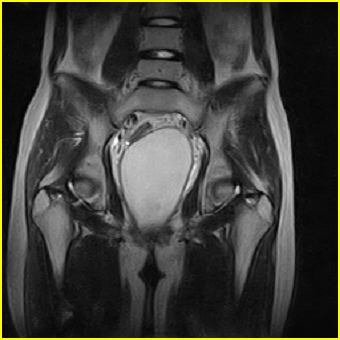

女、15岁、下腹疼痛2天,排尿困难1天。查体:处女膜闭锁,距处女膜约4至5cm处扪及一约5cm直径的圆形包块,张力较高,触痛明显、欠活动。b超提示子宫增大伴宫内增强回声团。

更正影像意见:阴道积血。

处女膜闭锁,阴道积血

处女膜闭锁,阴道积血,子宫积血.

处女膜闭锁,伴子宫及阴道积血.